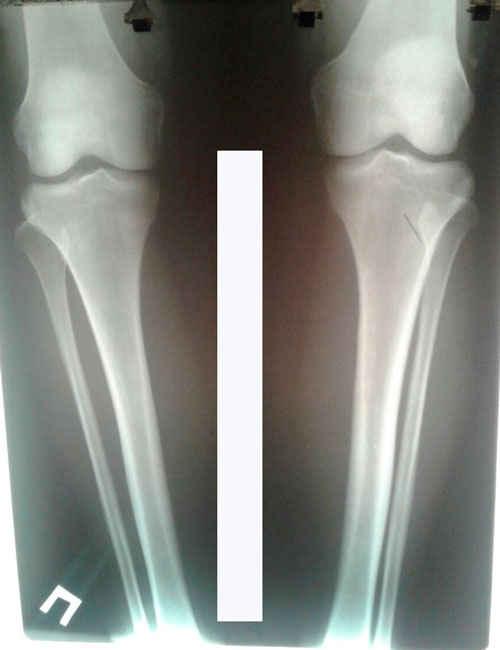

Исходник - 40 лет.

Дата операции - 28.03.2017г.

РЕНТГЕН ДО ОПЕРАЦИИ